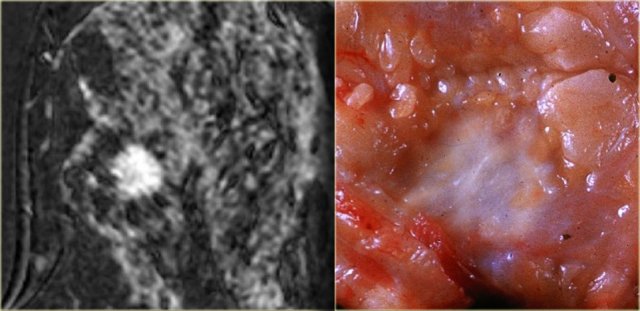

The image on the far left shows a spiculated mass, i.e. 80% chance of being malignant. .

Next to it the corresponding gross pathologic specimen.

You can see the spiculations invading the surrounding tissue in both.

Just like on mammography, this lesion is has a high likelihood of malignancy and would be labelled BIRADS 5.